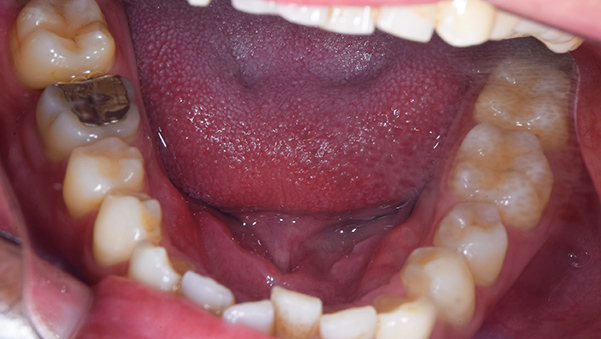

治療前:下の歯

担当医師所見:

下顎右側臼歯部には一見大きな問題はないように見えるが、 頰側にフィステルと言われる排膿路があり発赤と主張があり炎症状態が続いていた。